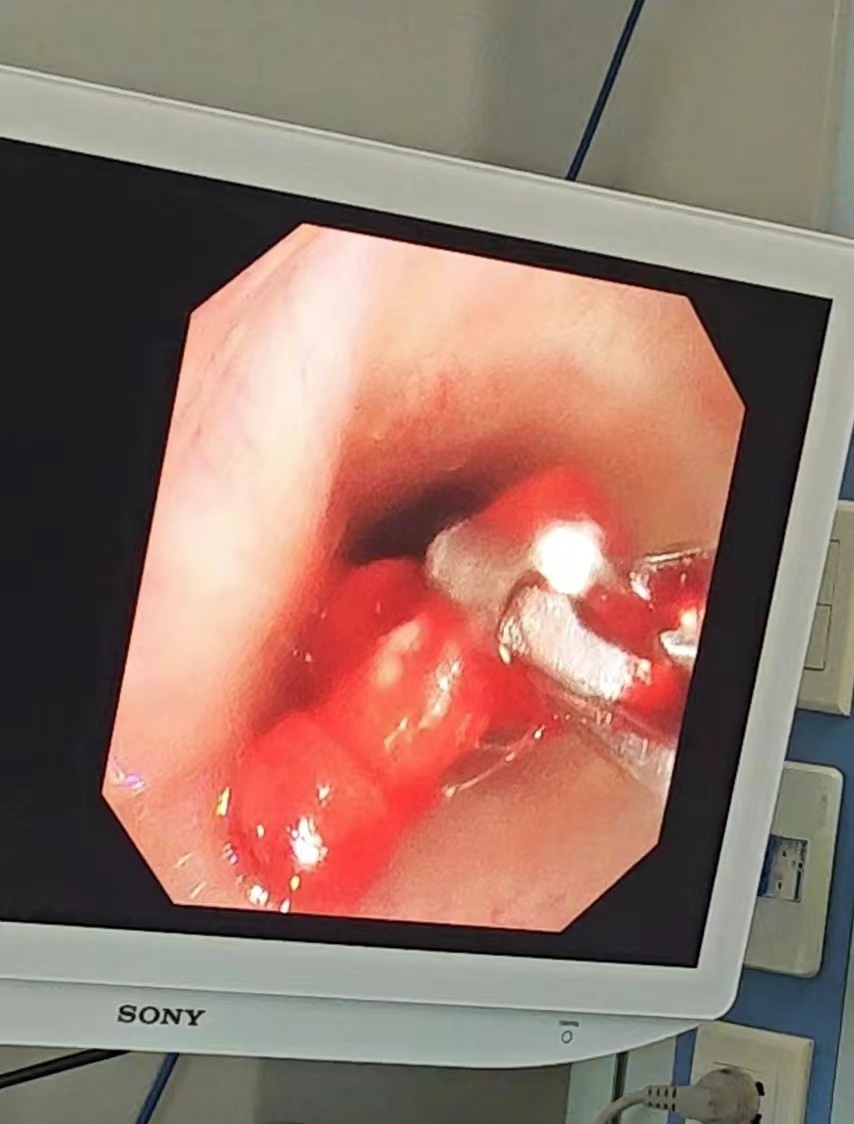

据了解,该患者为一名10岁男孩,在家咳嗽了2个多月,家长原本以为只是简单的呼吸道感染,但是在当地医院接受雾化吸入等治疗后仍不见好转,孩子的肺部CT也没能找到原因。在那之后,渐渐孩子在夜间出现了吼喘及胸闷,并且咳嗽似乎有加重的表现。7月27日,家长带孩子辗转来到了市第二人民医院儿科就诊,科室医生问诊后及时为孩子完善了气道三维重建等相关检查,突然发现孩子左主支气管有高密度影,起初医生怀疑可能是痰栓,为进一步明确高密度影性质,儿科副主任医师王瑞涛联合内镜诊疗中心、麻醉科,共同为该患儿做支气管镜检查,发现这团高密度影实际上竟然是一红色积木块!孩子咳嗽两个多月的罪魁祸首终于找到。